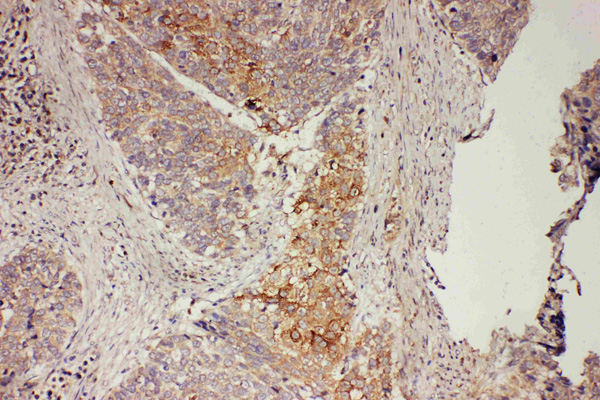

IHC (Immunohistochemistry)

(Anti-GRB7 antibody, AAA45711, IHC(P)IHC(P): Human Oesophagus Squama Cancer Tissue)